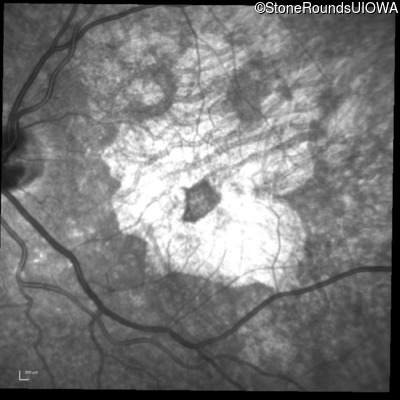

Infrared Fundus Photograph - Right - 20/32 +2

Exemplar

Infrared Fundus Photograph - Left - 20/20 -2